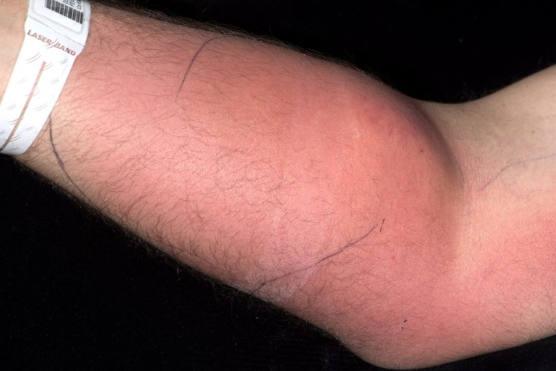

เมื่อไม่นานมานี้หนุ่มชาวไอร์แลนด์วัย 33 ปีคนดังกล่าว ต้องเข้าโรงพยาบาลในเมืองดับลินอย่างเร่งด่วน เนื่องจากมีอาการปวดหลังเป็นอย่างมาก และแพทย์ก็พบว่าแขนข้างหนึ่งของเขามีผื่นแดงและมีอาการบวมอย่างเห็นได้ชัด

และเมื่อทำการตรวจสอบร่างกายของเขา แพทย์ก็พบกับอสุจิที่ตกค้างอยู่ในแขน เนื่องจากเขาฉีดเข้าไปเพื่อหวังรักษาอาการปวดหลัง แต่มันกลับทำให้เขาติดเชื้อจากเซลล์เนื้อเยื่ออักเสบ